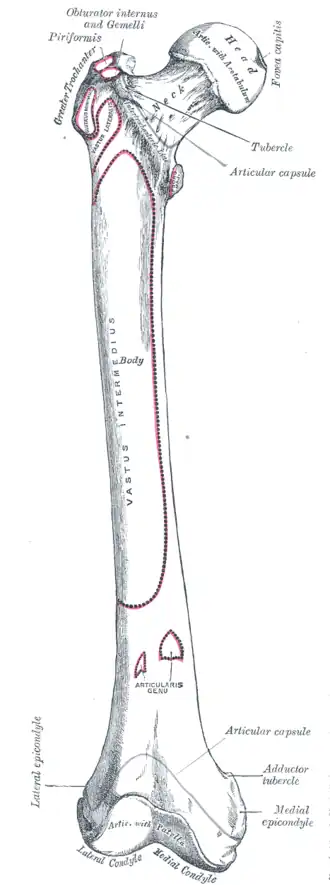

Right femur. Anterior surface.

Right femur. Anterior surface. -